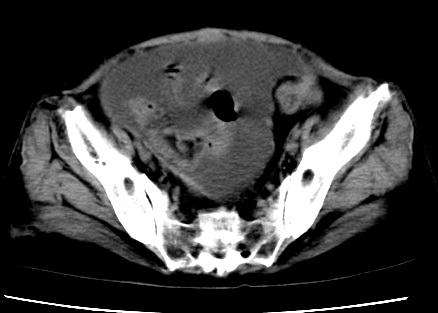

标题: CT23975:女61岁,腹部不适,明显消瘦

既往5年前卵巢癌行子宫及附件切除,右乳癌术后一年,考虑腹膜转移?

大量腹水,考虑腹膜转移。肝脏低密度灶。1囊肿,2转移。

1)结合病史,考虑腹膜及网膜转移瘤。2)肝脏多发性低密度灶,不排除转移瘤。3)大量腹水。

考虑卵巢癌行子宫术后复发,并肝、腹腔 、大网膜转移可能性大。

大量腹水。